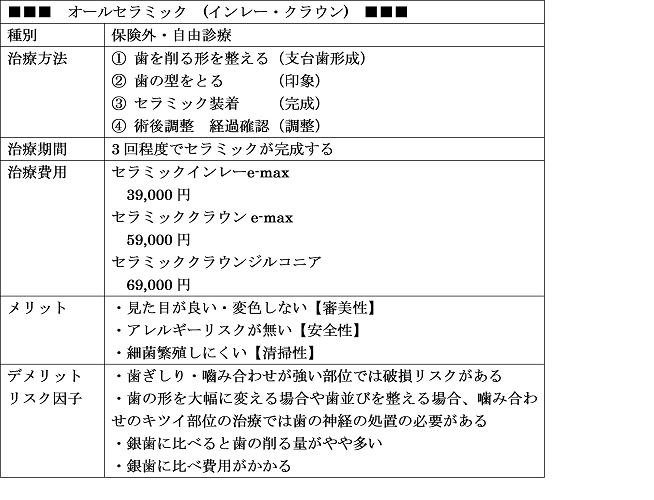

①きわだつ白さの汚れにくく耐久性抜群【プレミアムセラミックジルコニア】

②透明感のある自然な仕上がり【ナチュラルセラミックemax】

※オールセラミック(e-max ジルコニア)については国内歯科技工所にて作成依頼

をしており国内で承認されてない 未承認医薬品医療機器の使用はありません。

医療広告ガイドラインに基づき記載いたします、費用は2020年現在のものとなります。

前歯はオールセラミック(e-max,ジルコニアボンドセラミック)

が機能性・耐久性・審美性の面でゴールドスタンダード

オールセラミック 利点

金属アレルギーリスクがない

審美性 見た目が天然歯よりキレイ

歯ぐきが黒くなりにくい

オールセラミック 欠点

費用がある程度かかる